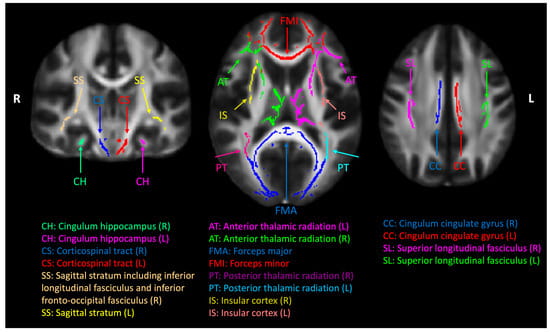

Cerebral white-matter tract regions of interest (ROIs). A common white-matter skeleton was first generated by the tract-based spatial statics (TBSS) toolbox in the FMRIB Software Library (FSL) using normalized diffusion tensor imaging (DTI) factional anisotropy maps from all the subjects. The white-matter skeleton was intercepted with Johns Hopkins University (JHU) white-matter tract atlas, and eighteen ROIs were used in this study.